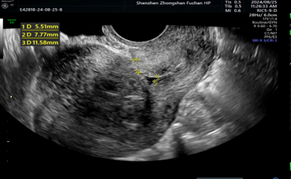

超声报告上写得明明白白:粘膜下子宫肌瘤,足足5cm大!

医生团队一看:

开腹?

虽然稳妥,但李女士还有“造人”计划呢!

为了最大程度保护她的“小房子”(子宫健康),不影响未来当妈妈,果断推荐了宫腔镜微创手术——创伤小、恢复快、保生育!